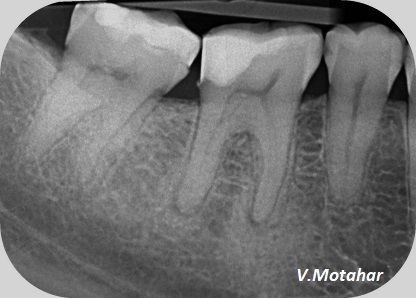

Root Canal treatment on Lower molar tooth immediate after the Root Filling!

before

after